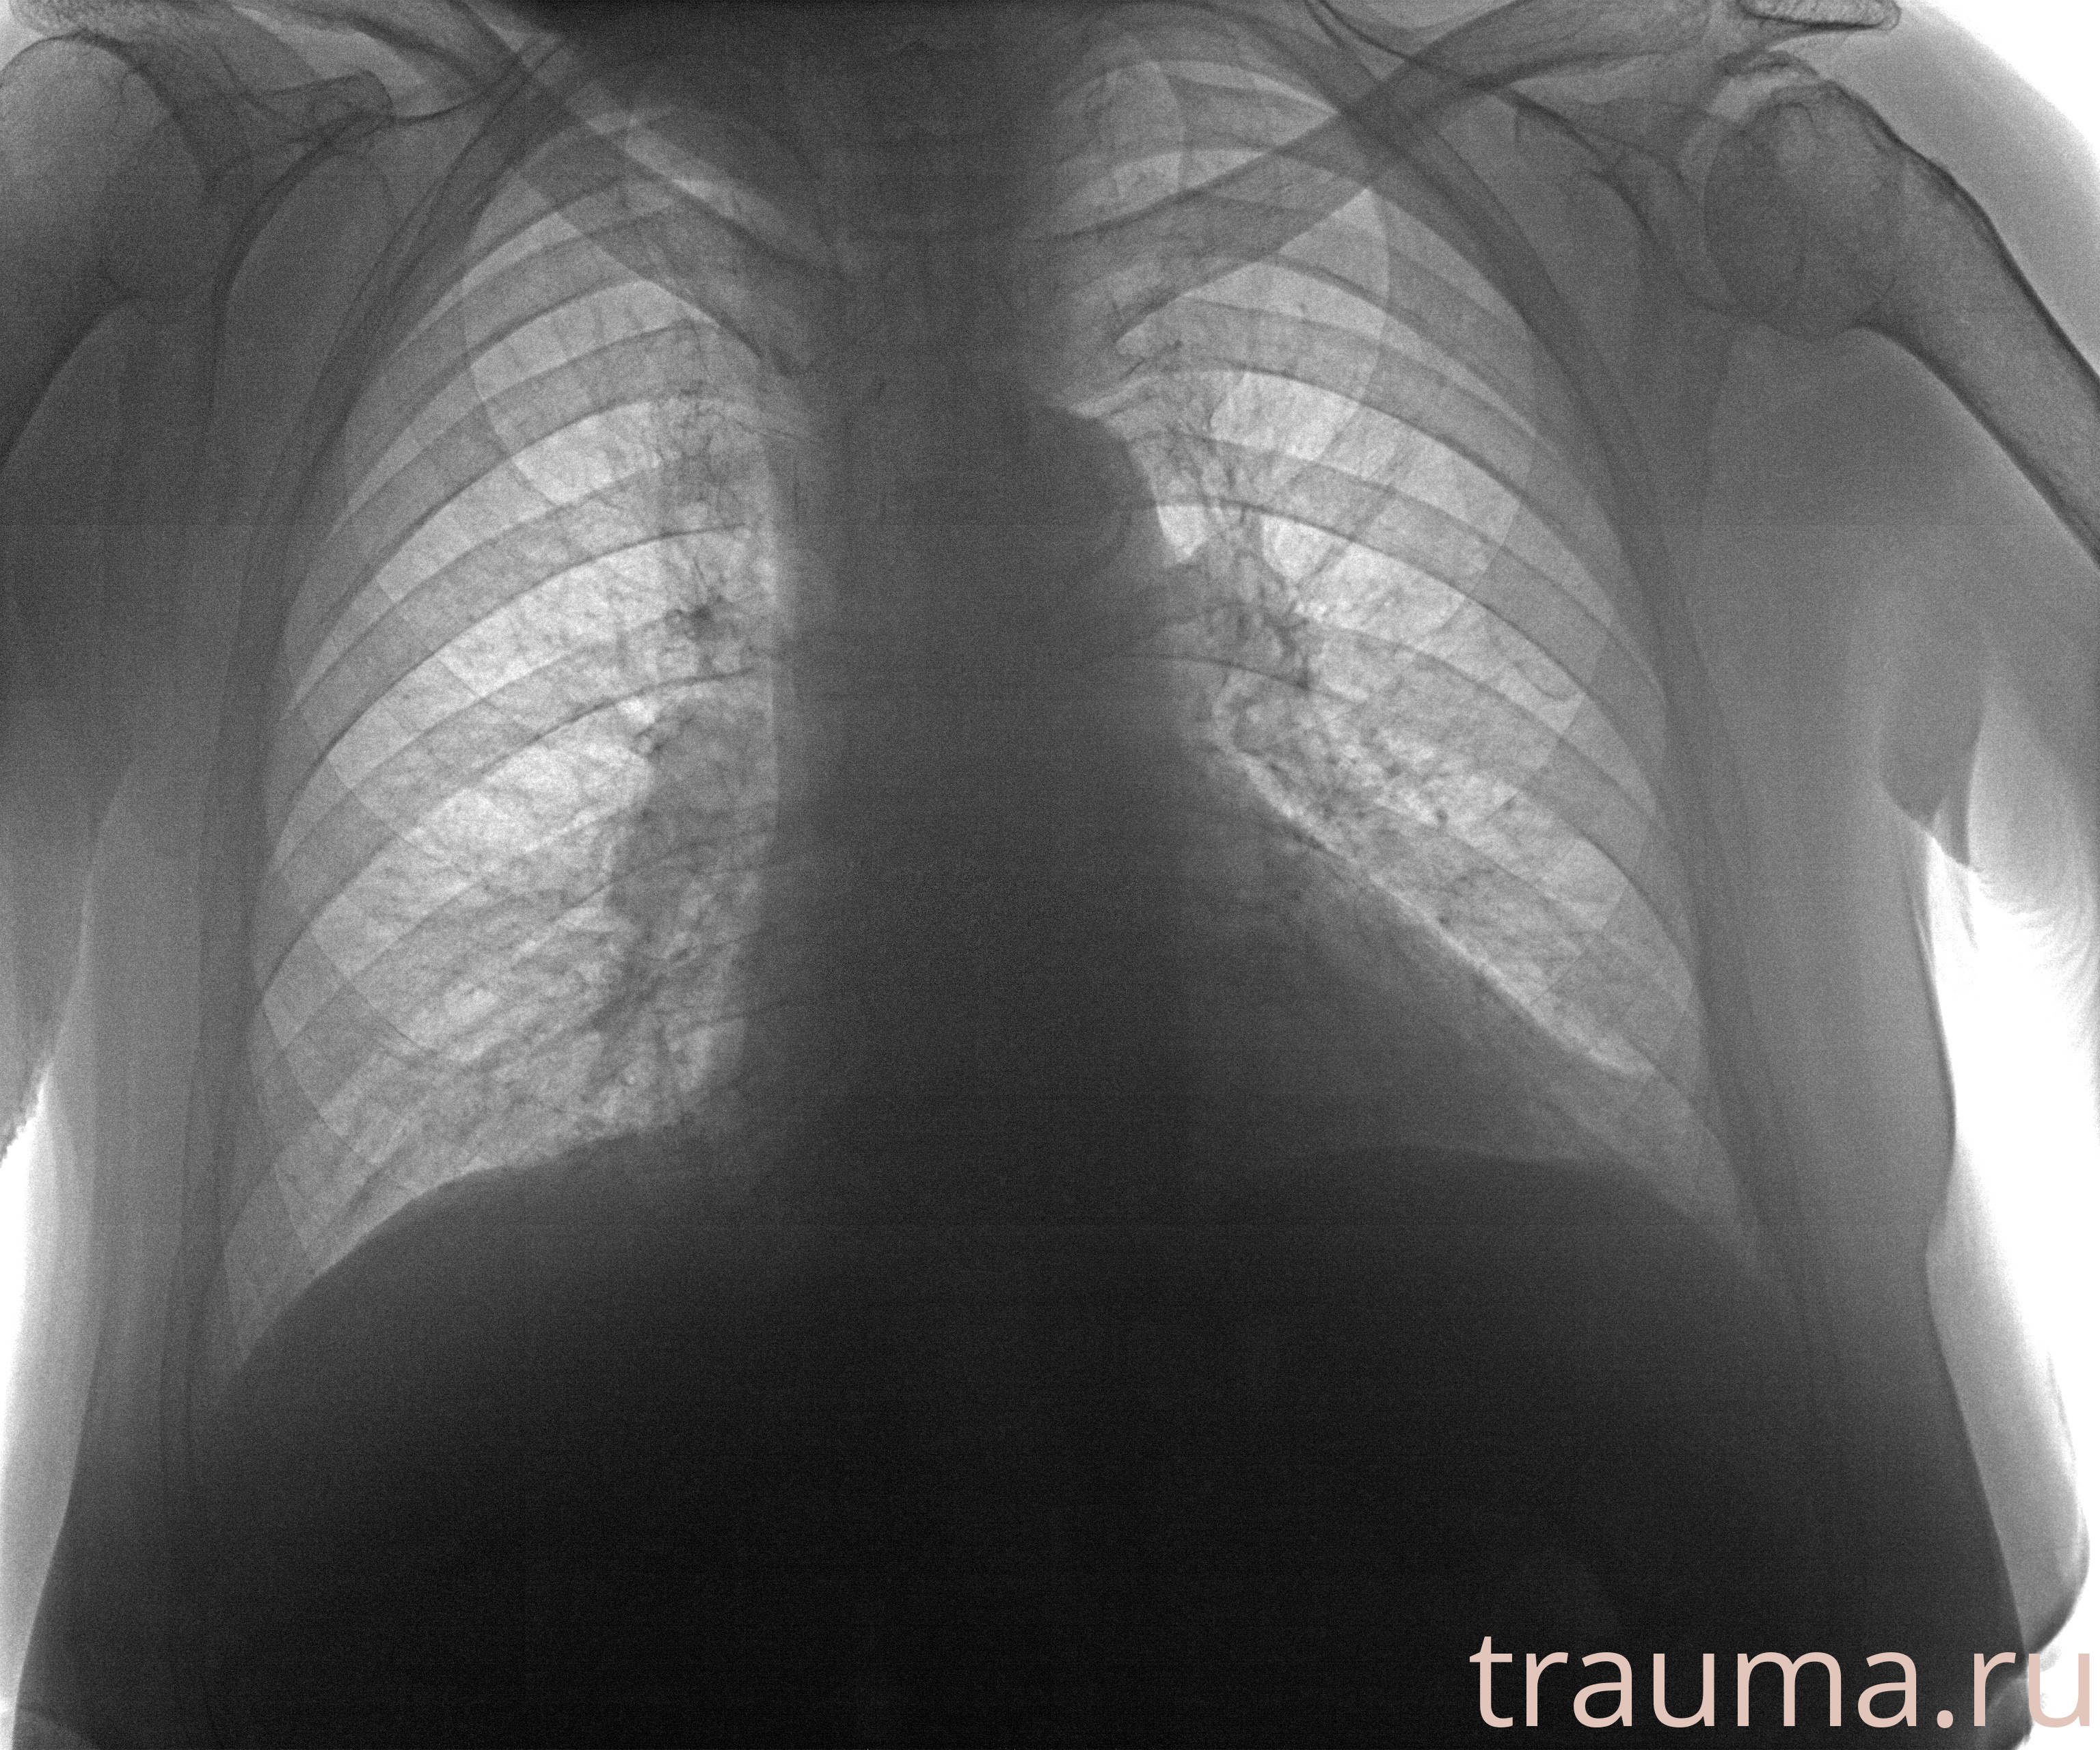

Рентген на дому: по вашему адресу приезжает врач-рентгенолог, травматолог-ортопед с мобильным рентгеновским аппаратом, проводит диагностику травмы или заболевания, делает необходимые рентгенограммы, дает рекомендации по дальнейшему лечению. Получить качественные снимки в домашних условиях возможно благодаря уникальной методике, разработанной МосРентген Центром для института  Склифосовского

при переломе шейки бедра и пневмонии от компании МосРентген Центр - партнера Института имени Склифосовского